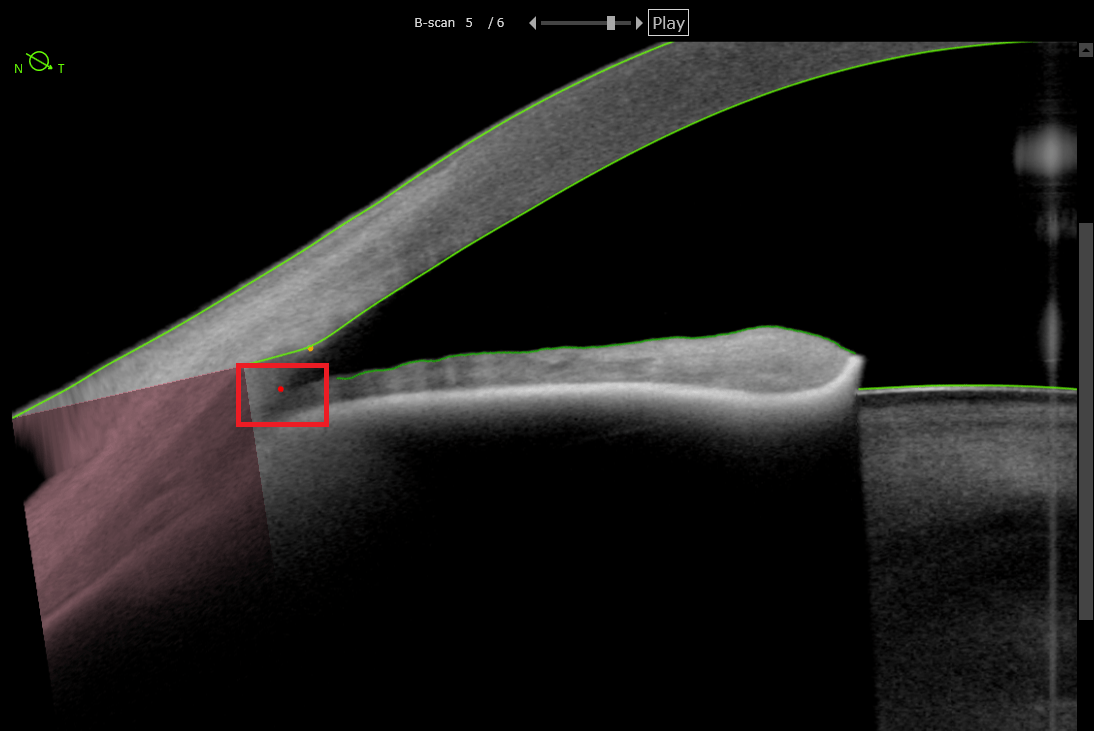

Changes between OCT section images are shown as contrast in the OCTA Section image, signaling this with a yellow overlay.

What is blood flow?

What is the Avascular Complex?